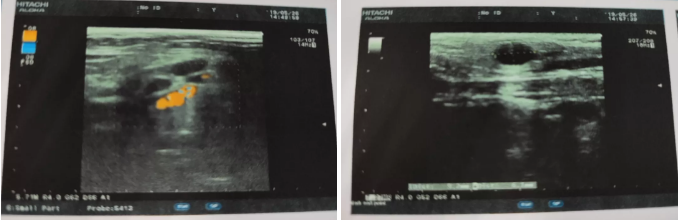

患者超声检查报告

强烈的不适感迫使他四处求医,经过多方的打探、对比,毛先生决定到成都寻求进一步的治疗。5月24日,毛先生来到了成都仁品耳鼻喉医院。经过详细的病史问诊与系统的检查发现,患者左侧外耳道高度肿胀,还伴有大量淡红色新生物堵塞......门诊专家 以“左耳中耳癌、左侧面神经麻痹V级、左耳混合性耳聋”将他收治入院,准备进行再次手术治疗。